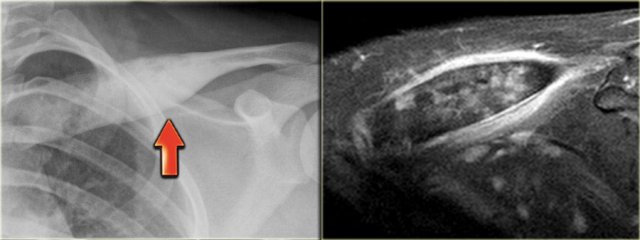

Chondrosarcoma (10)

On the left a typical broad-based osteochondroma arising from the proximal humerus.

The major part of the bony protrusion consists of fatty bone marrow.

There is a thin peripheral cartilage cap, i.e. no suspicion for malignant degeneration.